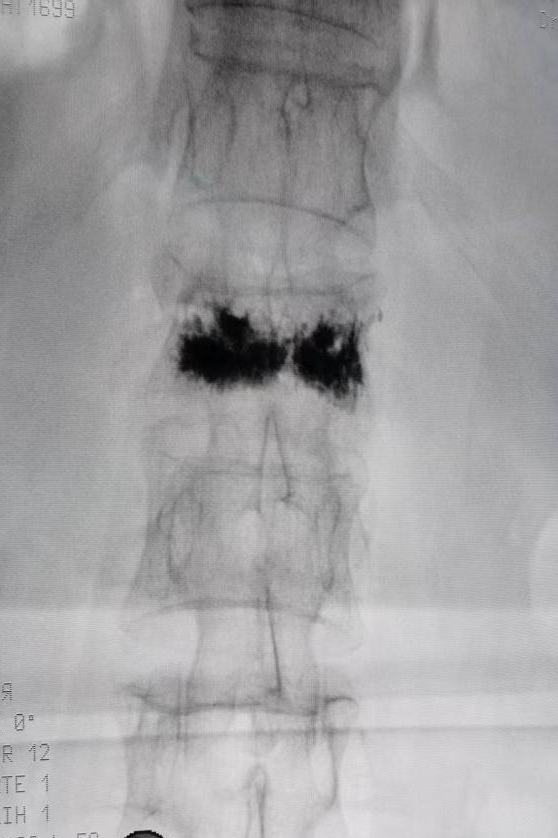

第1椎腰压缩骨折正位x线片、侧位x线片(箭头所示)